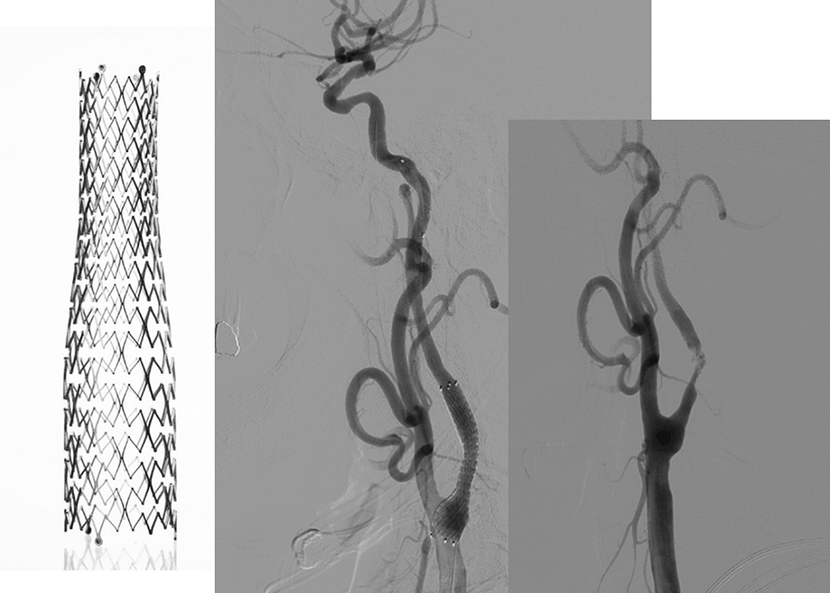

뇌MRA 와 뇌혈관조영술에서 좌측내경동맥의 심한 협착이 보임

성형술과 스텐트 삽입술을 시행하여, 우측의 수술전 사진과 비교시, 혈관을 넓혀주어 추가적인 뇌경색을 예방